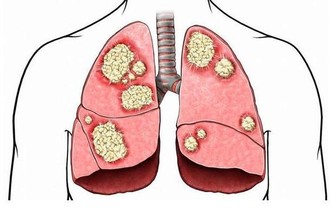

對於中年女性來說,除了常規的體格檢查外,還要格外重視乳腺超聲或乳腺鉬靶檢查,宮頸塗片檢查,這兩項檢查可以幫助女性,及時發現潛在的癌細胞,畢竟乳腺癌和宮頸癌對女性的傷害很大。當然,年過50歲後,還要注意檢查糞便潛血,以及腸鏡檢查。

對於中年男性來說,除了常規的體格檢查外,還要非常注重前列腺、膀胱超聲檢查,最好再抽血進行PSA檢查,看是否有患前列腺癌的風險。另外,有吸煙史的人最好要做低劑量螺旋CT檢查,年過50歲還要做腸鏡檢查和糞便潛血檢查。